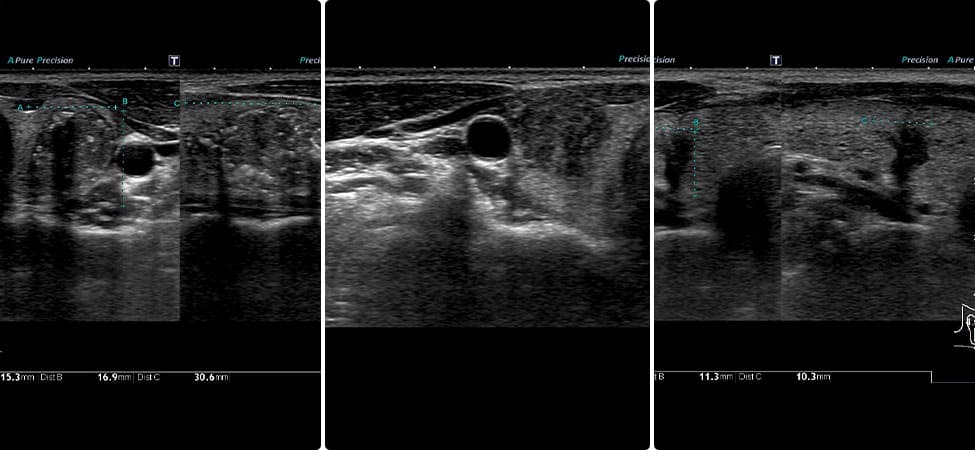

エコー所見では、上面は甲状腺被膜で隔たれていることを反映して白い線がみられます。副甲状腺のう胞では白い線が不明瞭なことがあります。

甲状腺のしこりの鑑別として、甲状腺の背側にある副甲状腺の病気が挙げられます。正常の副甲状腺はエコーでは描出できませんが、腫瘍、のう胞などでは甲状腺のしこり、のう胞と鑑別を要します。

⑤副甲状腺腺腫、副甲状腺のう胞